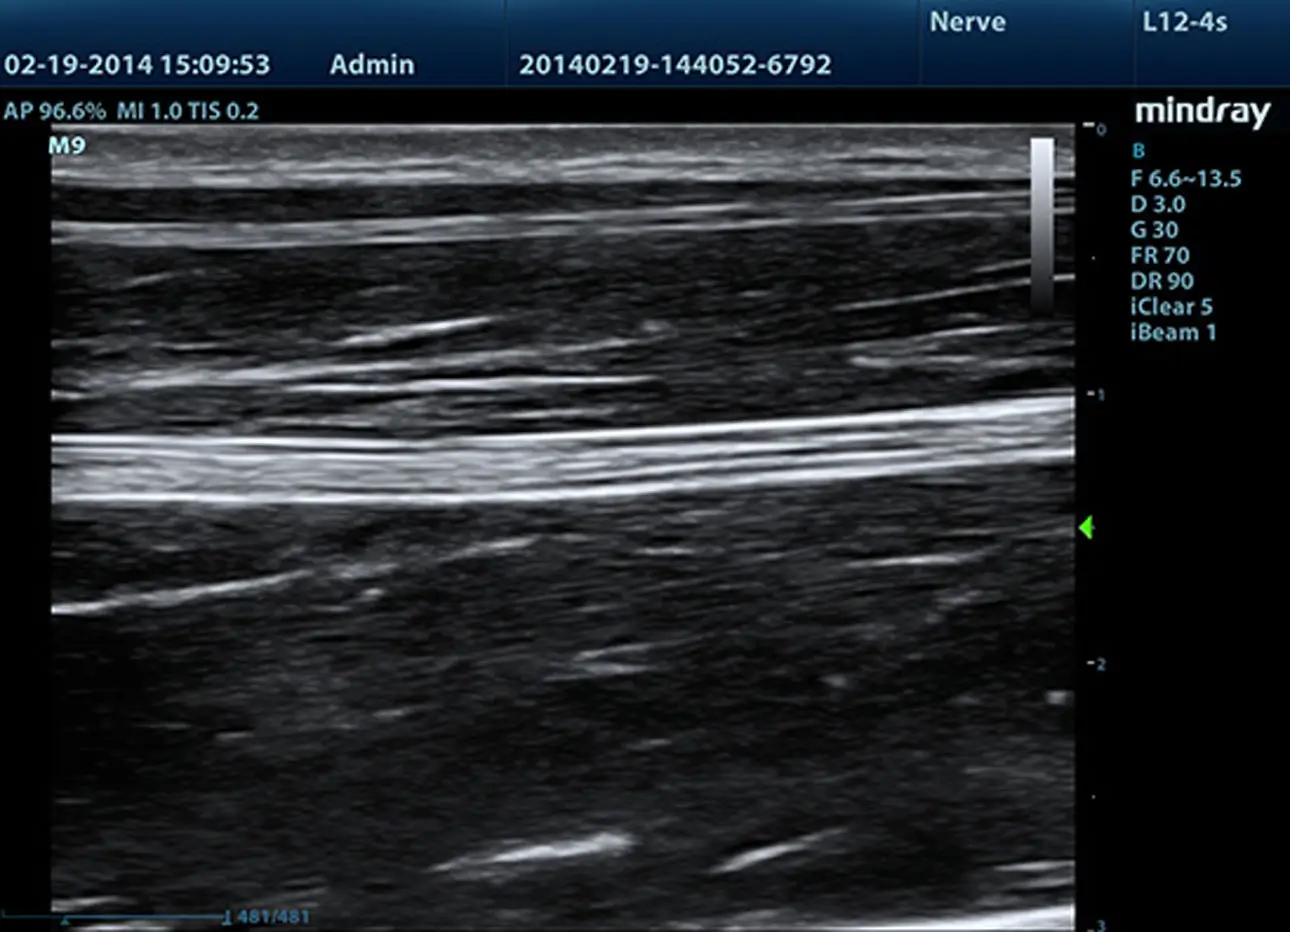

Zaawansowane elementy do przesyłania i odbierania sygnału zapewniają wysoką czułość i dokładność wykrywania echa. Innowacyjne technologie zastosowane w sondach pozwalają na lepszą penetrację i wyższą rozdzielczość, co znacznie poprawia możliwości diagnostyczne.

iBeam™ (obrazowanie krzyżowe)

Funkcja ta pozwala wykorzystywać skany wykonane pod różnymi kątami do stworzenia pojedynczego obrazu, co daje wzmocnienie rozdzielczości, kontrastu i lepszą wizualizację.